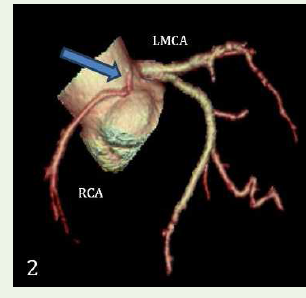

Case 1: A 70-year-old female with c/o dyspnea on exertion, case

of hypertension and diabetes mellitus, demonstrated an anomalous

origin of Right coronary artery from le coronary sinus, RCA seen

passing between the pulmonary trunk & ascending aorta– Malignant

inter-arterial course of RCA.Case 2: A 36-year-old male smoker with c/o chest pain & positive stress test and without any comorbidities, demonstrated an anomalous origin of Le main coronary artery from non-coronary cusp with retro-aortic course.

Figure 2:3D volume rendered reformation shows anomalous origin of right

coronary artery from left coronary sinus. Note the narrow caliber and acute

angulation of RCA.